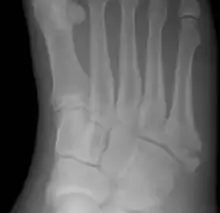

![]() | |

| Jones fracture as seen on Xray | |

A Jones fracture is a broken bone in a specific part of the fifth metatarsal of the foot between the base and middle part[8] that is known for its high rate of delayed healing or nonunion.[4] It results in pain near the midportion of the foot on the outside.[2] There may also be bruising and difficulty walking.[3] Onset is generally sudden.[4]

The fracture typically occurs when the toes are pointed and the foot bends inwards.[6][2] This movement may occur when changing direction while the heel is off the ground such in dancing, tennis, or basketball.[9][10] Diagnosis is generally suspected based on symptoms and confirmed with X-rays.[3]

Diagnostic X-rays include anteroposterior, oblique, and lateral views and should be made with the foot in full flexion.